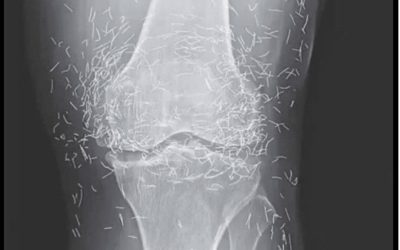

Na zdjęciu rentgenowskim kolan kobiety widać setki złotych igieł

Wyobraź sobie, że robisz sobie zdjęcie rentgenowskie z powodu bólu kolana... i odkrywasz, że twoje ciało kryje prawdziwy skarb! To…